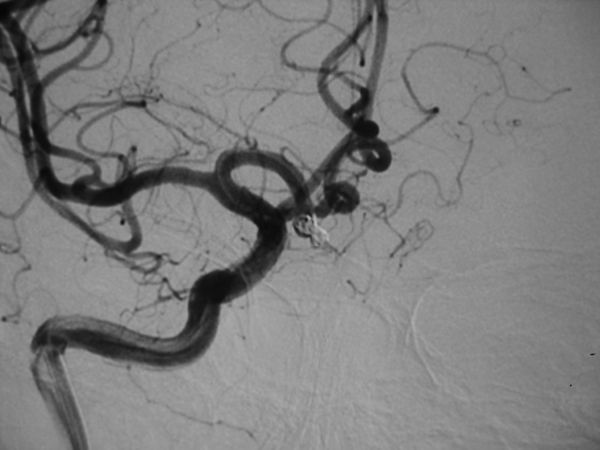

病例3、巨大动脉瘤栓塞:女性,66岁。左侧后交通巨大宽颈动脉瘤破裂出血,动脉瘤大小约7X8X10mm,患者意识模糊,脑肿胀明显,脑压极高,手术夹闭困难,为了防止动脉瘤再次破裂出血危及生命,孟祥靖主任带领全科医生经过仔细分析,决定采用支架辅助+弹簧圈栓塞的方法处理动脉瘤,3月20日孟祥靖主任、郭建主治医师在介入科、麻醉科的密切配合下,动脉瘤完全闭塞,目前,患者一般情况好,正在逐步康复中。

病例3:后交通巨大动脉瘤栓塞术前、后